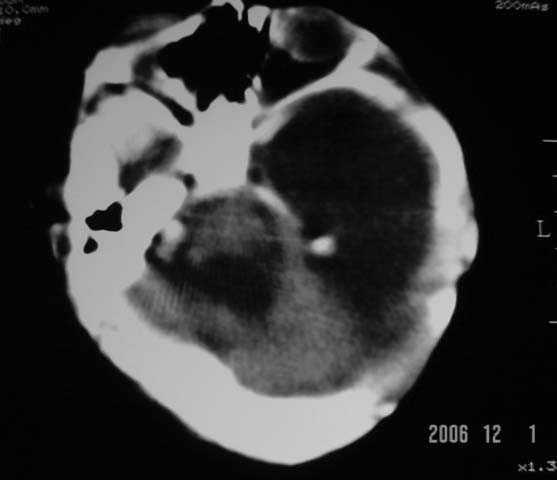

3m,出生时有新生儿吸入性肺炎、hie、化脓性脑膜炎,近一个月发现头围增大(51cm),无恶心呕吐。

第四脑室有增大,应该是交通性脑积水

3m,出生时有新生儿吸入性肺炎、hie、化脓性脑膜炎,近一个月发现头围增大(51cm),无恶心呕吐,脑室系统全程扩张,脑皮质变薄,结合病史考虑交通性脑积水

3m,出生时有新生儿吸入性肺炎、hie、化脓性脑膜炎,近一个月发现头围增大(51cm),无恶心呕吐,脑室系统全程扩张,脑皮质变薄,结合病史考虑重度交通性脑积水。